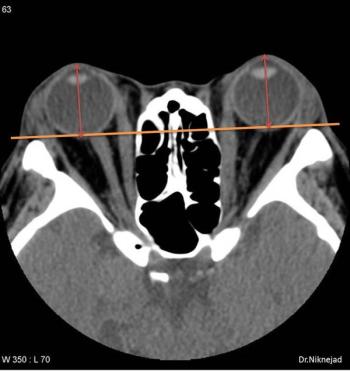

Greater imaging utilization has increased the prevalence of incidental findings or incidentalomas, but unclear clinical context and guidelines complicate management. Accordingly, these authors offer a thorough review of the literature and discuss new opportunities for improving interdisciplinary management strategies.